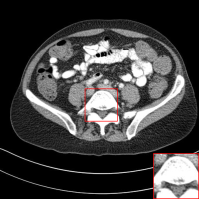

D.1 Low-Dose CT

In this subsection, we show the additional qualitative results on Low-Dose CT dataset authorized by Mayo Clinic [Moen etย al.(2021)Moen, Chen, Holmesย III, Duan, Yu, Yu, Leng, Fletcher, and McCollough] in Figure 13. As shown in Figure 13, previous methods tend to lose details and generate blurred results. However, our method removes the noise, while preserving the details of organs. It shows that our method is also practical for medical image denoising.

Figure 13: Qualitative results of our method and other baselines on Mayo Clinic Low Dose CT dataset. As shown in the highlighted red box, the reconstructed images by our method have few noise and preserve the details of organs. The display window is [160,240]160240[160,240] HU.